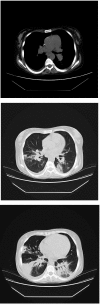

Respiratory distress and sudden death of a patient with GSDIb chronic neutropenia: possible role of pegfilgrastim